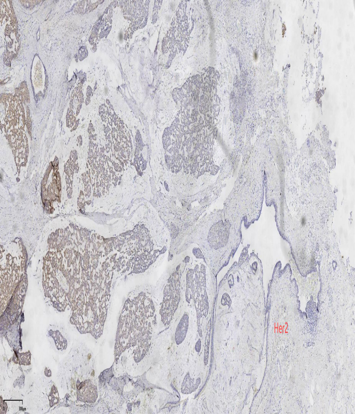

免疫组化

ER弥漫强+,Her2-,ki67低表达

具有神经内分泌表达:CgA、Syn(约70%的比例,阳性细胞表达不等)

ER弥漫强+,Her2无扩增